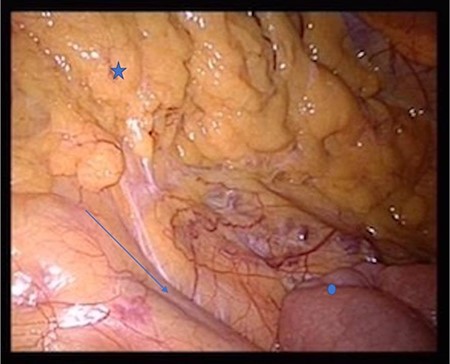

The patient was positioned supine. We used a 12-mm umbilical camera port, and 5-mm trocars were placed in the left and right middle abdomen. Laparoscopic inspection revealed a hernia aperture below the terminal ileum, behind which we found the hernia sac where the small intestine had become entangled 3 weeks previously (Fig. 3). The subsequent small bowel revision was uneventful. In the area of Treitz’s ligament, the vessels were on the right side with no herniation on the left side (Fig. 4). At this point, we decided to enlarge the hernia aperture by mobilizing the cecum. The ureter and the testicular vessels were identified. Finally, the hernia sac was widened, to prevent future entrapment of the small intestine. (Fig. 5) The postoperative course was uneventful and the patient was discharged 2 days later.

Star: transverse colon under the greater omentum, arrow: vessel axis, circle: proximal jejunum. The ligament of Treitz is not shown